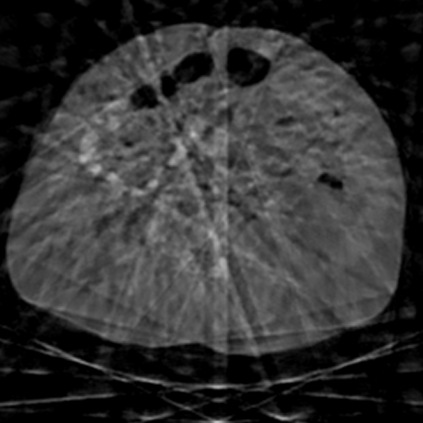

Sparse-view computed tomography (CT) -- using a small number of projections for tomographic reconstruction -- enables much lower radiation dose to patients and accelerated data acquisition. The reconstructed images, however, suffer from strong artifacts, greatly limiting their diagnostic value. Current trends for sparse-view CT turn to the raw data for better information recovery. The resultant dual-domain methods, nonetheless, suffer from secondary artifacts, especially in ultra-sparse view scenarios, and their generalization to other scanners/protocols is greatly limited. A crucial question arises: have the image post-processing methods reached the limit? Our answer is not yet. In this paper, we stick to image post-processing methods due to great flexibility and propose global representation (GloRe) distillation framework for sparse-view CT, termed GloReDi. First, we propose to learn GloRe with Fourier convolution, so each element in GloRe has an image-wide receptive field. Second, unlike methods that only use the full-view images for supervision, we propose to distill GloRe from intermediate-view reconstructed images that are readily available but not explored in previous literature. The success of GloRe distillation is attributed to two key components: representation directional distillation to align the GloRe directions, and band-pass-specific contrastive distillation to gain clinically important details. Extensive experiments demonstrate the superiority of the proposed GloReDi over the state-of-the-art methods, including dual-domain ones. The source code is available at https://github.com/longzilicart/GloReDi.